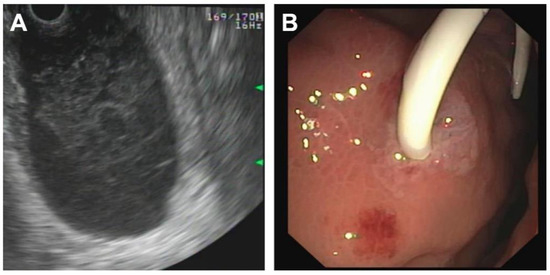

| Initial Management | Laparotomy, suture of the pancreatic head, distal pancreato-jejunostomy (Roux Y) | ERCP—complete dissection of the pancreas, Laparotomy, Jejunal repair, suture of the pancreatic head, distal pancreato-gastrostomy | ERCP—stenting of the ruptured pancreatic duct with 5 Ch pigtail drainage | ERCP unsuccessful, stenting of ruptured pancreatic duct not possible; chest drain (left side) |

| Management of complications | Anticoagulant therapy | - | Transgastric punction and drainage of pseudocyst with double-pig tail drain Ch 7, spontaneous dislocation of pig tail Antibiotic therapy Persistent fistula of the ruptured pancreatic duct, recurrent stenting (2 times), removal of stent after 5 months | Transgastric punction and drainage of pseudocyst with double-pig tail Ch 7, spontaneous dislocation of pig tail Antifungal therapy |